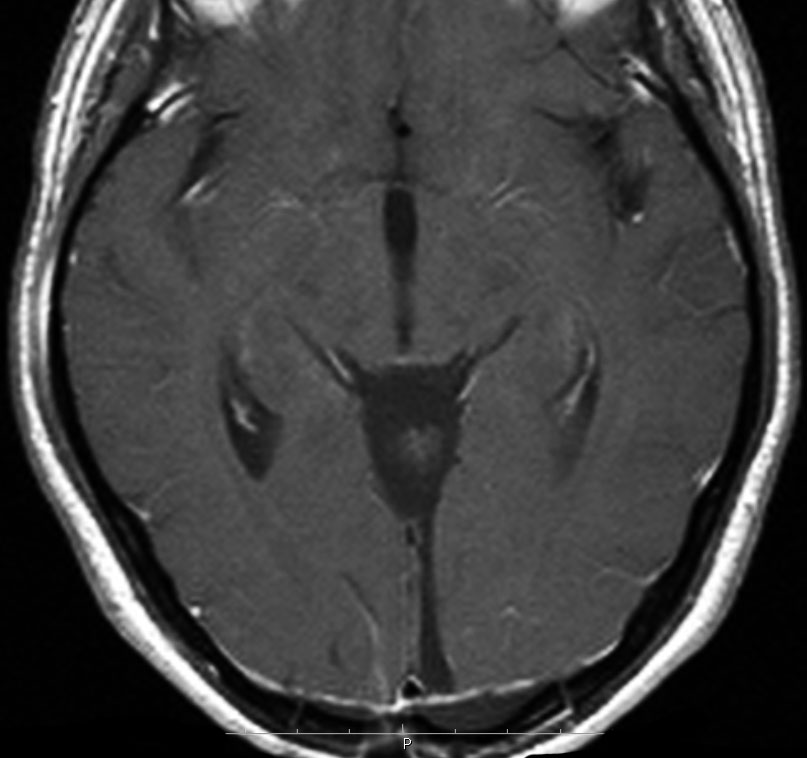

静脈洞交会髄膜腫 meningioma of the confluence of sinuses

若い女性に偶然発見されたものです。直静脈洞と静脈洞交会の接合部あたりに発生したもので,静脈洞はほぼ閉塞に近い所見でした。しかし,この部分の静脈洞は,テント硬静脈側副路が発達することがあるので,硬膜を含めた積極的な摘出をすることは絶対にできません。もしほんの少しでも流れがある直静脈洞を閉塞させると短時間に脳死になるような脳静脈圧亢進が生じる可能性があるからです。静脈洞内に少し取り残して(右下の矢印)手術を終了しました。手術後には定位放射線治療を行って再増大を防ぎます,